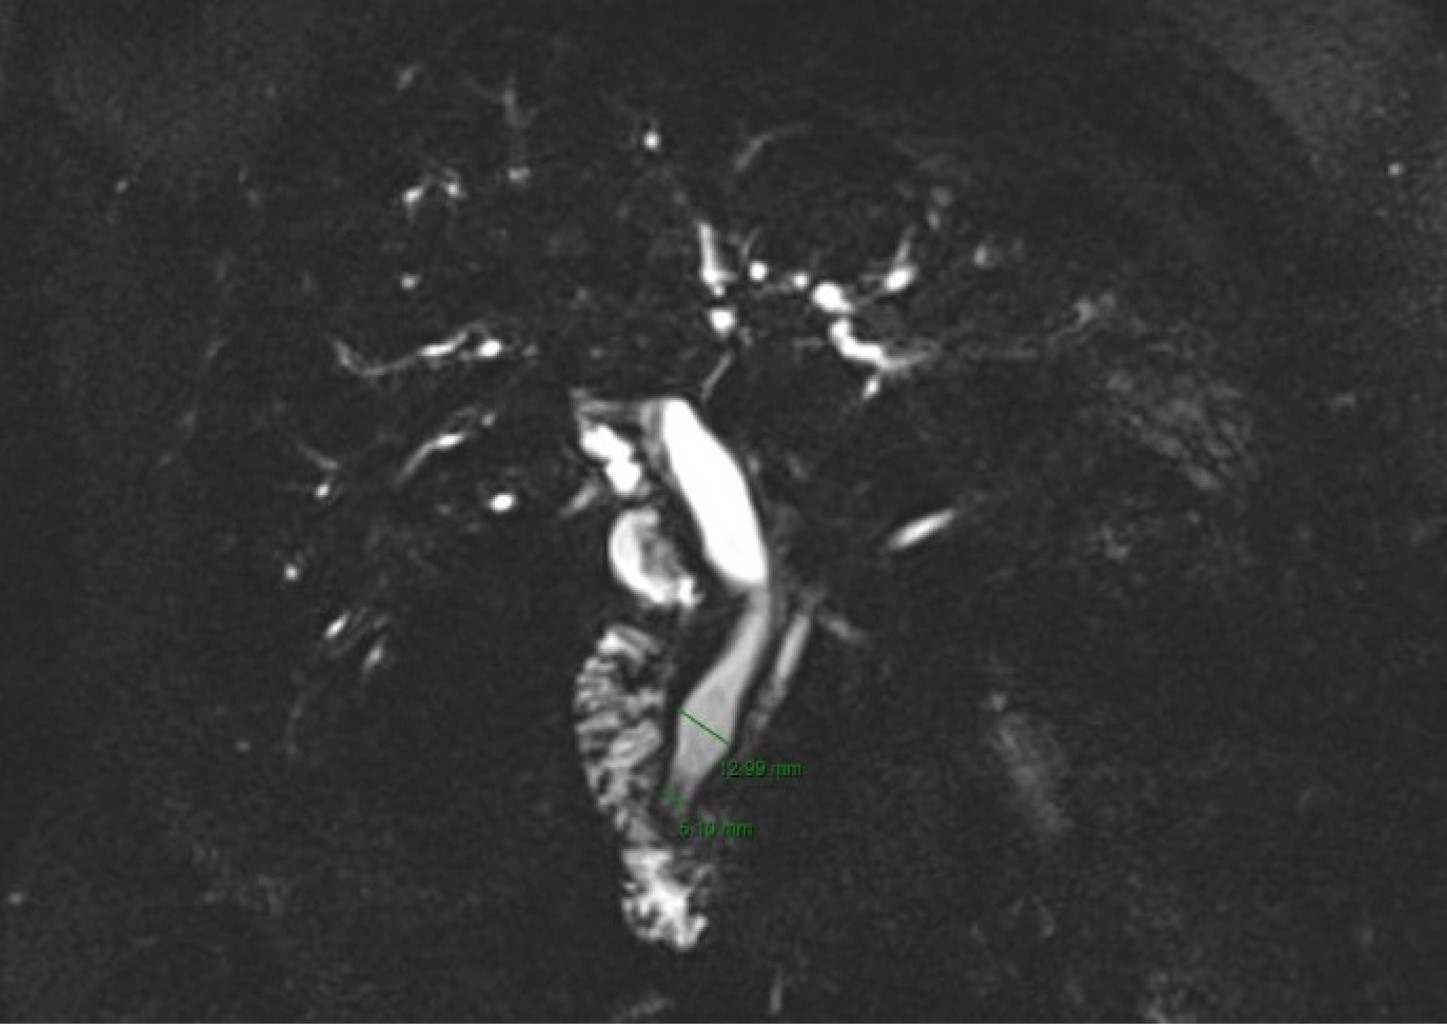

Mujer de 51 años con antecedente de colecistectomía laparoscópica hace 12 años, descenso gástrico, plastia hiatal y bypass gástrico de una anastomosis hace cuatro meses. Inició el padecimiento en su cuarto mes de posoperada de OAGB con pérdida de peso posterior de 18 kg. Acudió a urgencias por dolor en epigastrio transfictivo intermitente de 15 días de evolución, referido con intensidad 10/10 en escala visual análoga (EVA), acompañado de nausea y vómito, con presencia de ictericia y coluria. A la exploración abdominal se encontró dolor a la palpación superficial en epigastrio e hipocondrio derecho. Se le realizó biometría hemática y perfil bioquímico completo, y se reportaron leucocitos 7,780/mm3, linfocitos 0.23 × 103/μL, neutrófilos 7.21 × 103/μL, urea 19 mg/dL, BT 3.640 mg/dL, BD 3.290 mg/dL, TGP 592 U/L, TGO 821 U/L, FA 486 U/L, DHL 647 U/L, amilasa 12 U/L, lipasa 7 U/L. Se realizó colangiorresonancia magnética nuclear (CRMN), la cual reportó dilatación del colédoco, más evidente en sus porciones distales de hasta 12 mm con una zona redondeada hipointensa adyacente al esfínter de Oddi de 5 mm de diámetro (Figura 1), por lo que se procedió a realizar colangiopancreatografía retrograda endoscópica (CPRE) transgástrica guiada por laparoscopía.

Figura 1